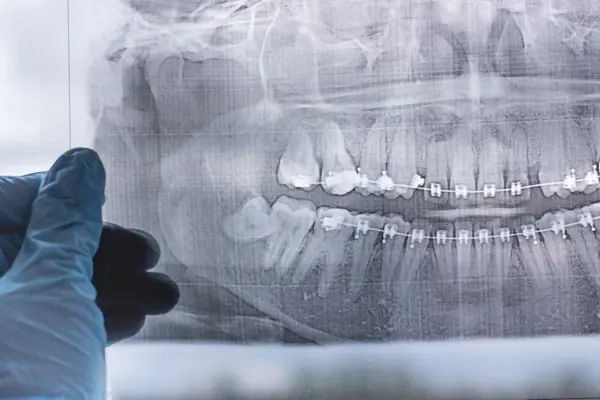

Before your procedure, our dentist will perform a thorough examination of your teeth, gums, and jaw to assess the position of your wisdom teeth. We may take X-rays to get a clearer picture of the teeth and their roots. This helps us determine the best course of action and plan your treatment accordingly.